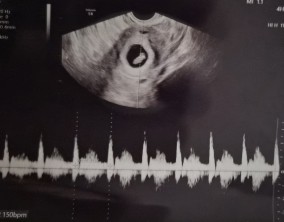

두 줄에서 심장소리까지, 따뜻하게 이어진 시간

이예흔 원장님을 비롯해 의료진과 선생님들 모두 친절하게 대해주셨고, 병원 전체 분위기도 따뜻해서 치료를 받는 동안 마음이 한결 편안했습니다. 그런 환경 덕분에 끝까지 치…

긴 치료 과정 동안 불안하고 지칠 때도 많았지만, 의료진 분들의 따뜻한 손길과 지속적인 응원이 큰 힘이 되었습니다. 그 덕분에 11주 4일 된 아기를 품고 이 순간을 맞이할 수 있었…